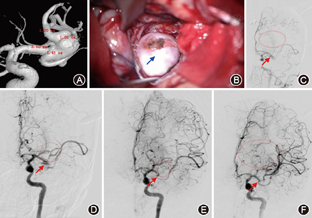

见图3。

见图4。

见图5。

如症状性颈内动脉闭塞,头颈副神经节瘤,复杂、难治性硬脑膜动静脉瘘与动静脉畸形,脑膜瘤等富血供脑瘤等,见图6,图7。